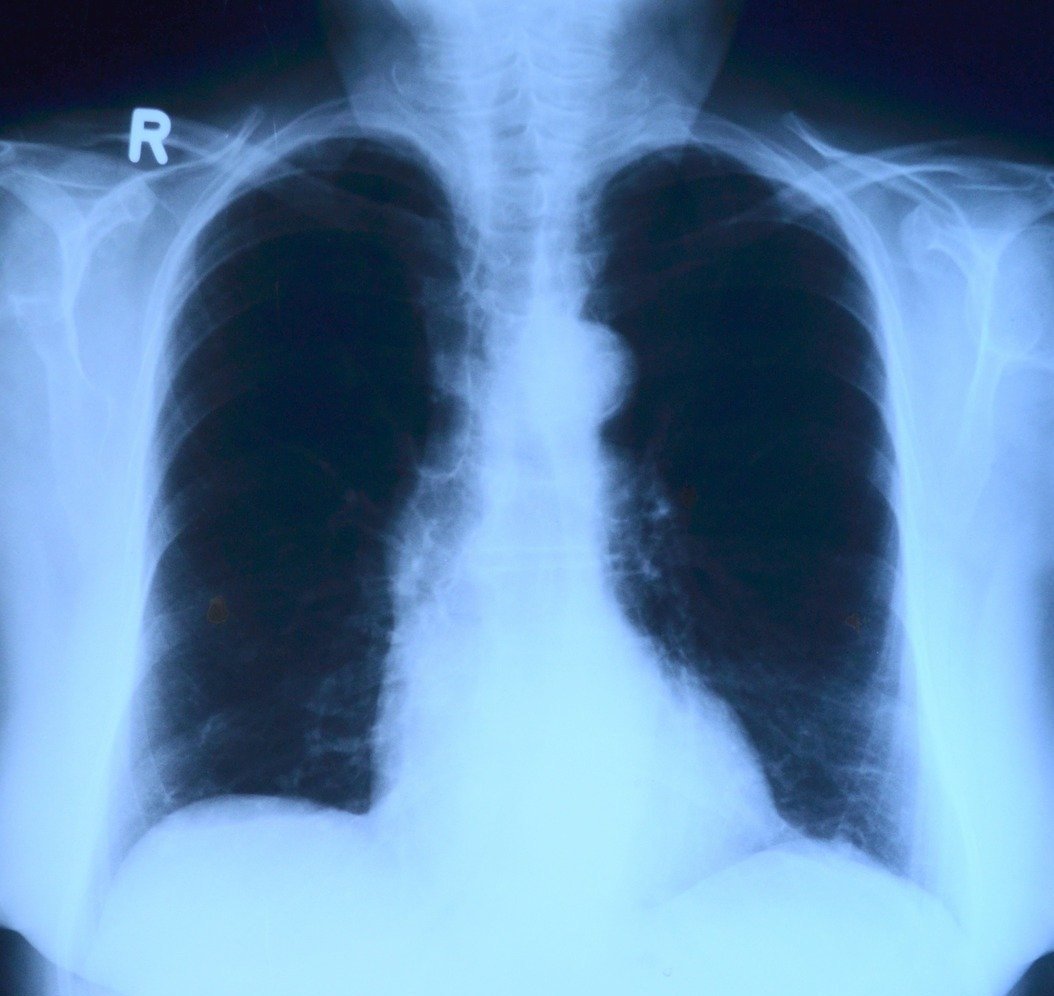

«Чем больше при COVID поражена легочная ткань, тем хуже ситуация. В ряде случаев она замещается грубой соединительной тканью, поэтому в легкие попадает меньше кислорода и начинаются проблемы с работой сердца и сосудов. Поэтому чем раньше выявили заболевание и начали лечение, тем меньше вероятность, что легкие будут глубоко поражены», — рассказывает Елена Волчкова.

Такие осложнения при пневмониях случаются, разумеется, не только при коронавирусной инфекции, но и при массе других. «Это бывает при гриппе, например, особенно, при пандемическом гриппе H1N1, который ходит в этом году тоже. Там тоже в некоторых случаях развиваются атипические пневмонии, при которых поражается альвеолярное древо. К сожалению, эти изменения носят необратимый характер».